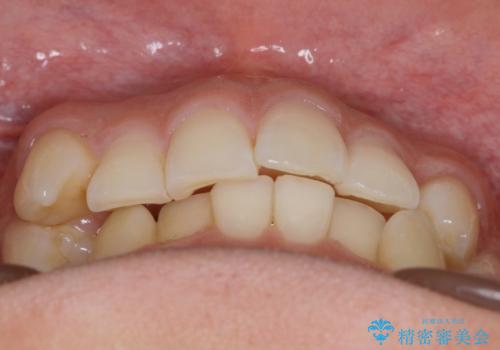

インビザラインで八重歯の治療

八重歯と噛み合わせえお治す必要がありましたが、抜歯を必要とするほどの状態ではなかったため非抜歯プランで治療を開始しました。